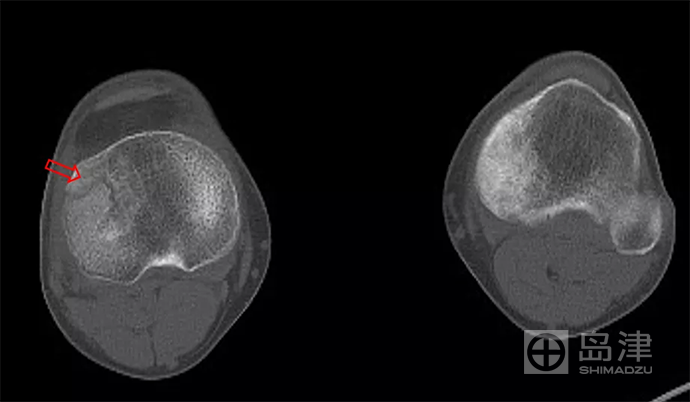

病例三:骨折征象显示

45岁男性,与孩子玩耍时,从一级台阶上蹦下即感右膝疼痛明显,无法行走。

右膝正侧位X线:未见骨折直接及间接征象 。

DTS 显示胫骨平台骨折 。

查 CT MR ,与DTS结果一致。

隐匿性骨折 DR无法发现

右胫骨平台隐匿性骨折

DTS可发现平片无法发现的骨折

CT结果与DTS一致

MRI结果与DTS一致

图像来源:西安市第九医院